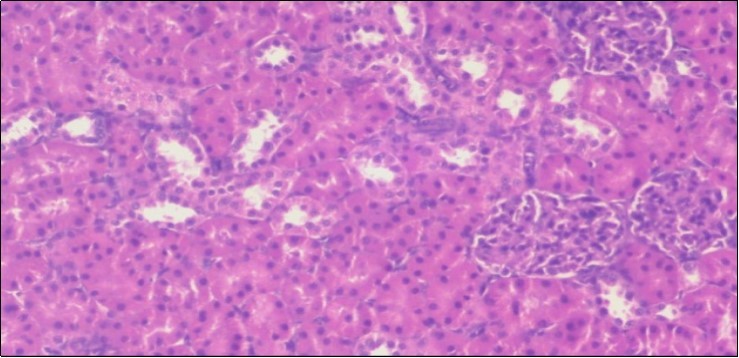

Effect of Ator, Fennel and Their Combination on the Liver of Obese Rats

The histological examination of the livers of control rats feeding standard diet showed normal architecture hepatocytes, blood sinusoid and central vein, figure 6. The rats which were fed on a (HFD), showed swollen hepatocytes with vacuolated cytoplasm filled with fatty infiltration, congested central vein and disappearance of blood sinusoids, figure 7. By comparison, the liver of rats that were treated by fennel after obesity and control mice observed nearly normal of the hepatocytes with eosinophilic cytoplasm, central vein and clear blood sinusoids and more bi-nucleated cells, figure 8. While examination of rats' liver that were treated by Ator and after the obesity appears, they showed mild fatty change in hepatocytes, few hepatocytes retain is eosinophilic cytoplasm and central vein figure 9. Liver of rats that were treated by fennel and Ator after obesity and control rats are showing nearly normal hepatocytes figure 10.

Figure 7.Photomicrograph of liver section of obese rat showing swollen hepatocytes with vacuolated cytoplasm filled with fatty infiltration, congested central vein and disappearance of blood sinusoids, (H&E) (40X).

Photomicrograph of liver section of obese rat showing swollen hepatocytes with vacuolated cytoplasm filled  with fatty  infiltration, congested central vein  and disappearance of blood sinusoids, (H&E) (40X).